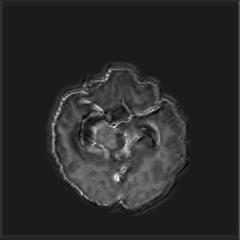

We argue that the sub-optimal paradigm of processing different abstractions within a single CNN pipeline can be remedied through the effective processing of information in a structured manner. Consequently, we devise strategies for disentangling the edge and texture information within a single training pipeline. Figure 2 illustrates how our proposed module, dubbed EG-CNN, can be paired with any existing CNN encoder-decoder to improve segmentation quality near intensity edges. We have applied our EG-CNN to the tasks of brain and liver tumor segmentation in medical images (Figure 3).

(1) Brain MR (2) Liver MR (3) Liver CT (4) Lung CT